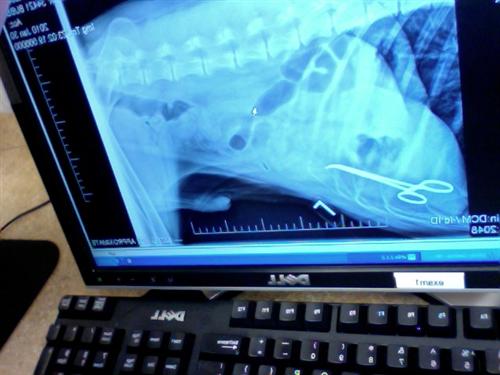

I just got an email from my friend - her dog has been sick for weeks, so they took him to the emergency vet hospital this past weekend and they did an x-ray.

The dog had surgery TWO years ago to remove something that got lodged in his abdomen that he ate. And this is what showed up in the xray. Apparently the vet left a surgical instrument in him, that has made him increasingly sick and has interfered with his bowel movements.

How horrible is that??? Image Attachment(s):